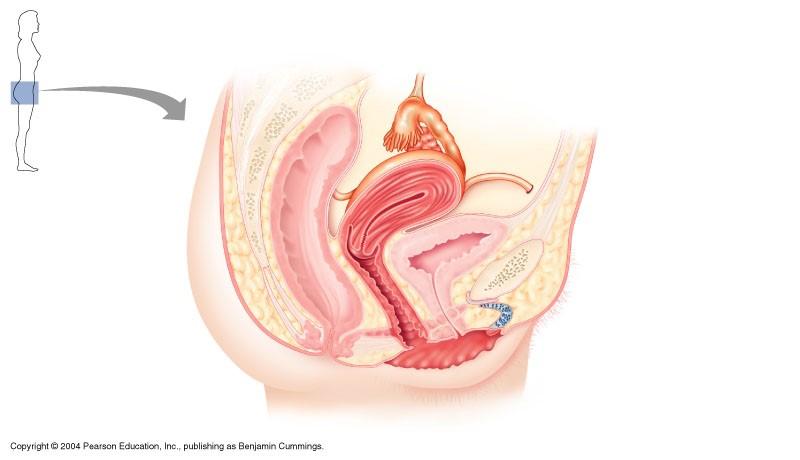

The indicated part of the female reproductive system is

cervix

the indicated part of female reproductive system is fundus of uterus

false

Female reproductive system

infundibulum

round ligament

cervix

vagina

uterosacral ligament

uterine tube